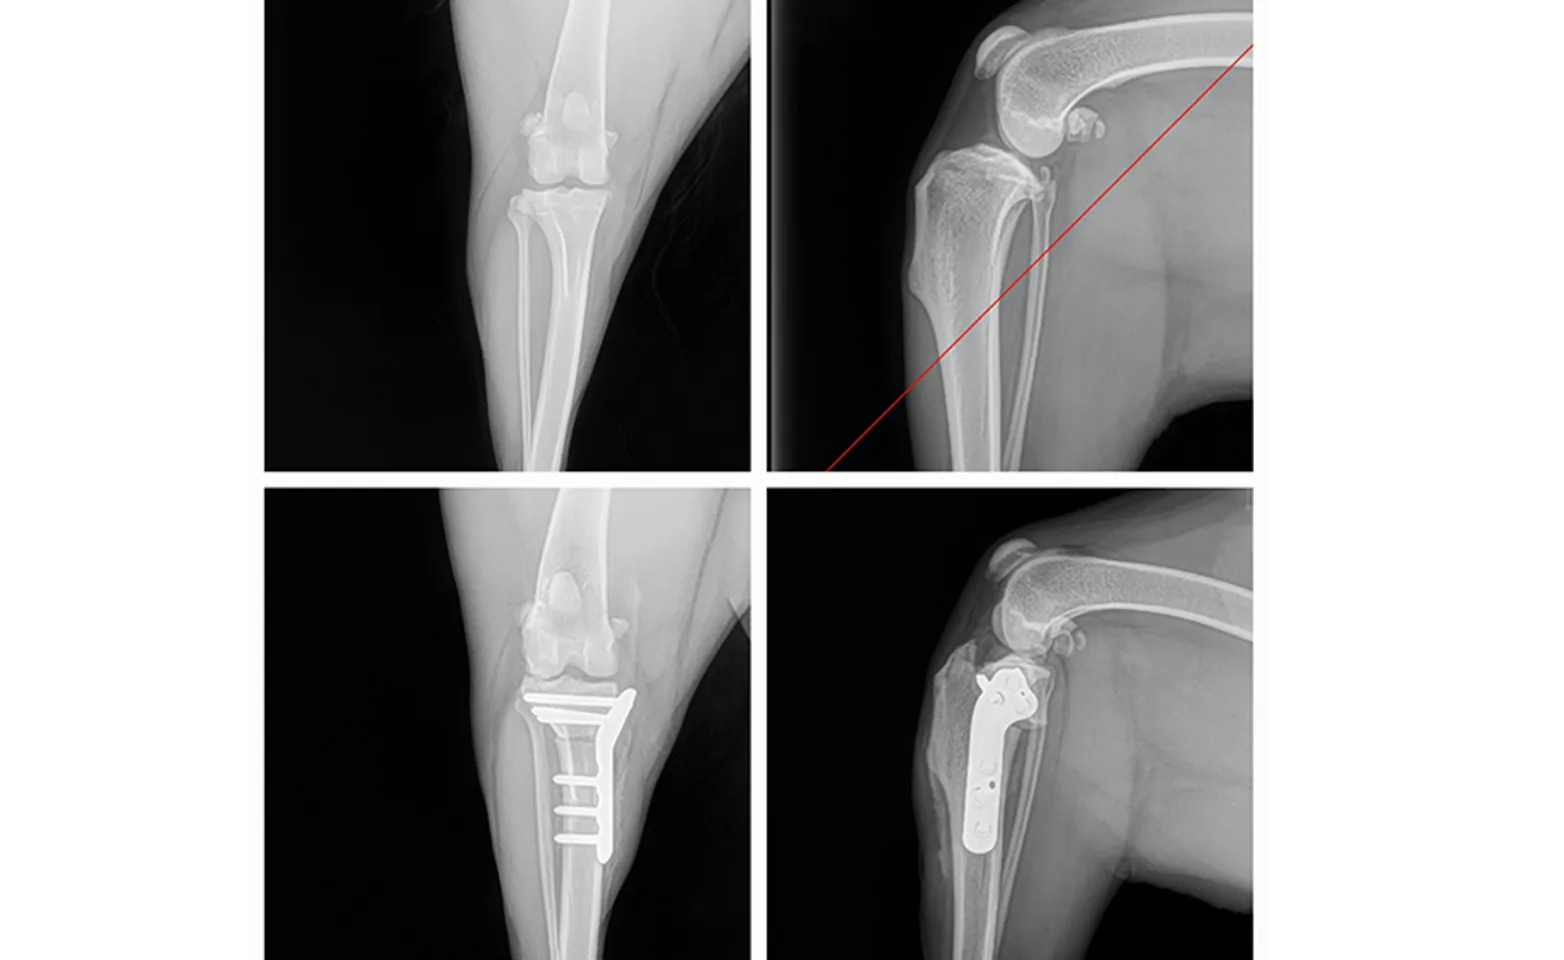

The TPLO (Tibial Plateau Levelling Osteotomy) is done to stabilize the knee joint after a cranial cruciate ligament tear. The procedure changes the geometry of the joint to stabilize the joint during weight bearing by switching the primary joint stability from the damaged cranial cruciate ligament to the patellar tendon and the cauda cruciate ligament.

The joint is then closed and the tibial plateau is cut with a circular saw and then rotated to approximately 6 degrees, a small pin is placed to allow testing. If stability, range of motion, and alignment are normal, a bone plate is contoured and screwed to the bone for stabilization. Post-op radiographs are then taken to assess the tibial plateau slope. The limb is then bandaged and ice is applied during recovery to help minimize pain and swelling.